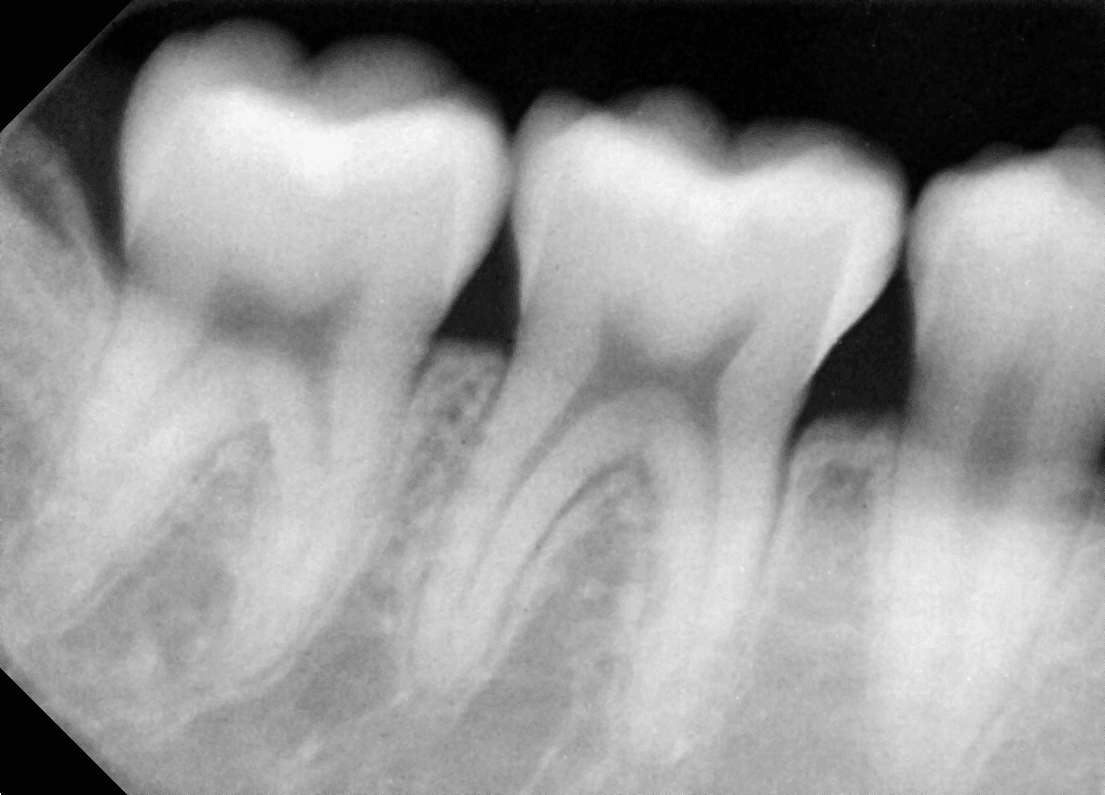

건강 상담 질문사랑니 발치 후 음식 끼임2월 8일

발치 후 음식 언제부터 가능한가요? (부산 30대 중반/여 사랑니 발치 후 음식 끼임)

사랑니 발치 후 음식은 언제부터 먹어야 하나요?

이를 뽑고 발치 후 음식 끼임이 생기면 어떻게 빼야 할까요?